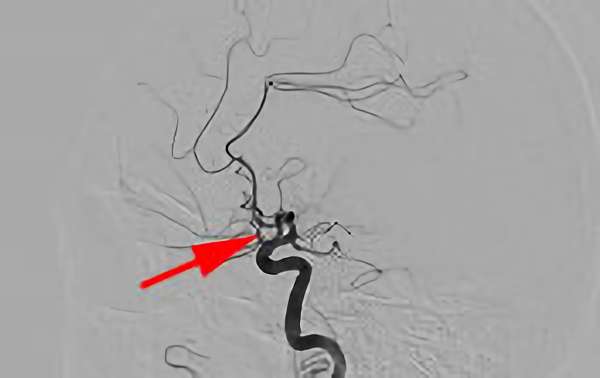

右内頚動脈 後交通動脈 分岐部動脈瘤

60代

院内外来

No.520 手術前

No.520 手術中

No.520 手術後